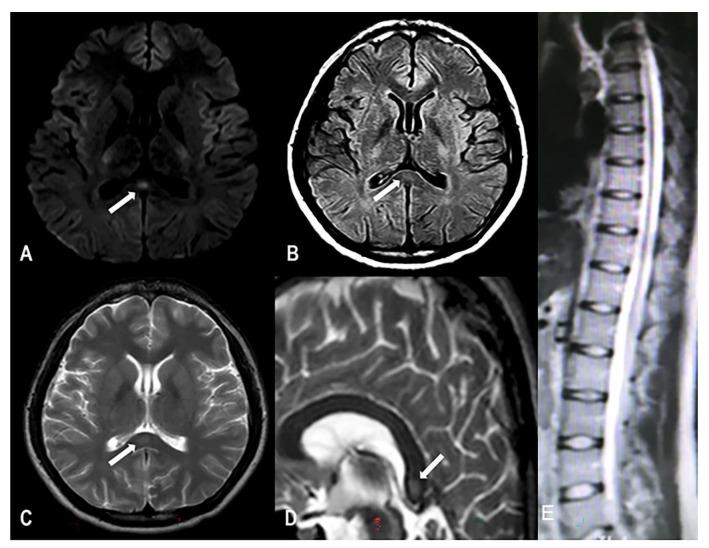

An 18-year-old man with no previous history of neurological or psychiatric disorders presented to our hospital with headache, intermittent blurred vision, and limb weakness after 150 days of recreational nitrous-oxide abuse. The patient's serum vitamin B12 concentration was normal, and magnetic-resonance imaging (MRI) examination revealed isointensity on T1-weighted imaging (T1WI) of the corpus callosum and high signal intensity on T2WI, T2FLAIR, and diffusion-weighted MRI (DWI); thus, a diagnosis of RESLES was established. The patient received 0.5 mg of mecobalamin daily and nitrous oxide was discontinued. After 4 weeks, the patient's symptoms disappeared and the imaging examination revealed normal findings.

一名18岁男性,既往无神经或精神疾病史,在滥用笑气150天后因头痛、间歇性视力模糊和肢体无力就诊于我院。患者血清维生素B12浓度正常,磁共振成像(MRI)检查显示胼胝体在T1加权成像(T1WI)上呈等信号,在T2WI、T2液体衰减反转恢复序列(T2FLAIR)和扩散加权MRI(DWI)上呈高信号;因此,确诊为RESLES。患者每日接受0.5mg甲钴胺治疗,并停用笑气。4周后,患者症状消失,影像学检查结果正常。